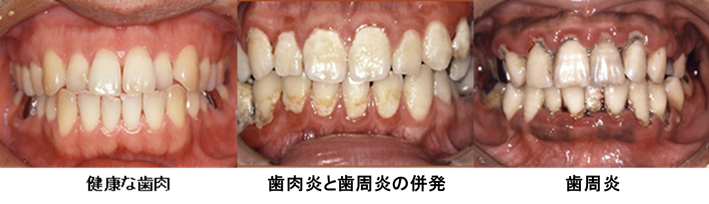

上の写真は、実際のお口の中の写真ですが、左から健康的な歯肉の状態、歯肉炎になってしまった状態、歯周炎になってしまった状態のものです。

健康的な状態では、歯肉の色が健康的な淡いピンク色を呈しており、歯と歯の間の歯肉もピンと尖った状態で張りがあり、いかにもきれいですね。

ところが、歯肉炎を起こしてしまいますと、歯の周囲の歯肉は赤く腫れプラークがびっしり付着しているのがわかります。このようになりますと、歯磨きのような軽度の刺激でも痛みがあったり、簡単に出血をするようになってしまいますし口臭も強くなってきます。

一方、右の写真のように歯周炎を起こしてしまうと、歯と歯茎の境目に黒い色をした歯石がびっしりと付着し、その影響で歯ぐきは赤黒く腫れあがりブヨブヨとしてきますし、歯が揺れてきたり、痛くて噛めないといった症状も現れてきます。

このように非常にひどい状態になれば、どなたにも気づいていただけるのですが、実際には、ここまでひどく見えないにもかかわらず非常に進行してしまっているものがほとんどで、軽度や中等度の状態では気づいていただけないというのが現実なのです。